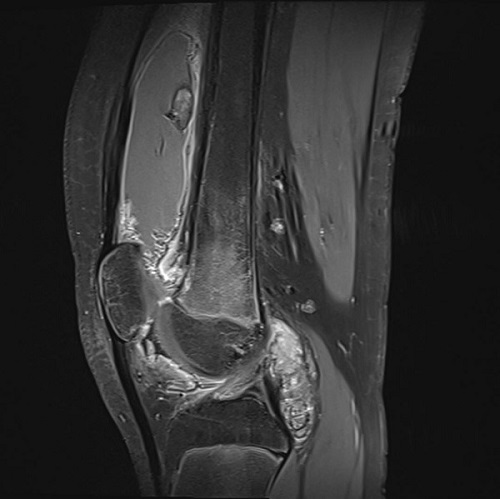

Se derivó a Reumatología Pediátrica, que decidió el ingreso hospitalario para completar el estudio. Durante el mismo, se realizó una artroscopia, con hallazgos de elevación de hematíes y leucocitos en el líquido sinovial y cultivo negativo. La resonancia magnética mostró un marcado derrame articular que distendía de forma significativa la bursa suprapatelar, así como un engrosamiento sinovial difuso y depósitos de hemosiderina, sugestivos de sinovitis villonodular pigmentada (Figura 2). Para confirmar el diagnóstico se practicó una biopsia articular, cuyo estudio histopatológico resultó inespecífico y orientó inicialmente a un proceso reumático. Ante la discordancia diagnóstica, se analizó la muestra mediante un panel genético dirigido a fusiones del gen CSF1, frecuentes en la SVNP, y se identificó la fusión CSF1::FN1, confirmatoria del diagnóstico de sinovitis villonodular pigmentada.

| Figura 2. Sinovitis villonodular pigmentada |

La resonancia magnética constituye la técnica más sensible y específica para orientar la sospecha diagnóstica de SVNP, al evidenciar engrosamiento sinovial difuso y depósitos de hemosiderina hipointensos, considerados característicos de la enfermedad6,7. Sin embargo, en la edad pediátrica la histología puede ser inespecífica, lo que dificulta el diagnóstico definitivo1,2. En este contexto, la biología molecular ha adquirido un papel clave: la identificación de fusiones del gen CSF1, en particular, la fusión CSF1::FN1, resulta altamente específica y permite confirmar la enfermedad en casos dudosos8-12.